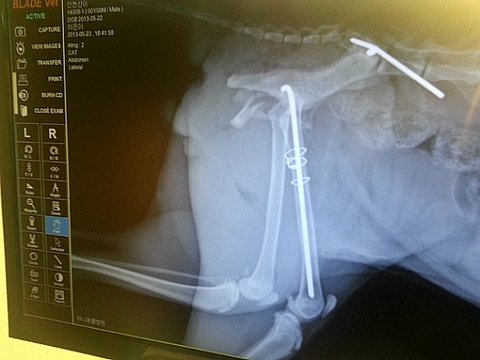

골반골절/대퇴골절 수술후 일주일 사진주의 [신이]

대퇴골절, 골반골절, 안락사 판정... 교통사고로 제게 온 길고양이... 신이...

교통사고를 당해 대퇴부 및 골반골절로 안락사 판정을 받았고 주인 없는 길고양이 신이가

할수 있는건 아무것도 없었어요. 수술이 잘된다해도 배변장애와 후지마비의 가능성 또한

선생님들의 긴 회의끝에 병원에선 신이를 수술해서 살리기로 결정하였고 그렇게 네달의 긴 입원기간...

'수술후 신이의 모습은 정말 처참하고 안쓰러워 눈물밖에 안나왔습니다.